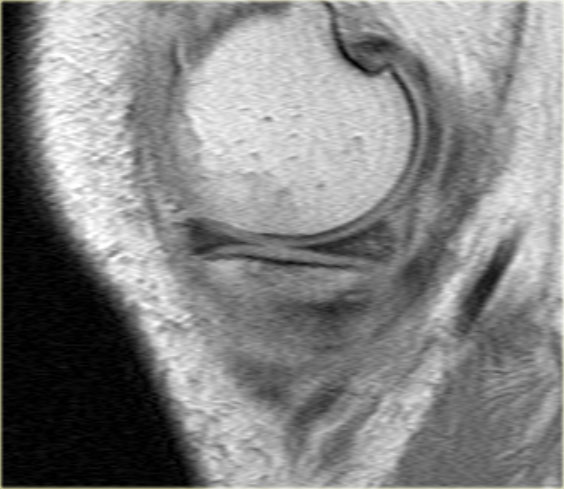

Bên trái là một trường hợp khác của sụn chêm ngoài bị lật.

- Lưu ý sừng trước rất lớn.

Phần trong là sừng sau đã bị di lệch. - Phần trong chạy vào hố gian lồi cầu.

- Phần bị di lệch được nhìn thấy rõ ràng như là ‘cấu trúc thứ ba’

trong hố gian lồi cầu. - Điểm nối với phần còn lại của sừng sau.

- Điểm nối với phần còn lại của sừng sau.

- Phần còn lại rất nhỏ của sừng sau.